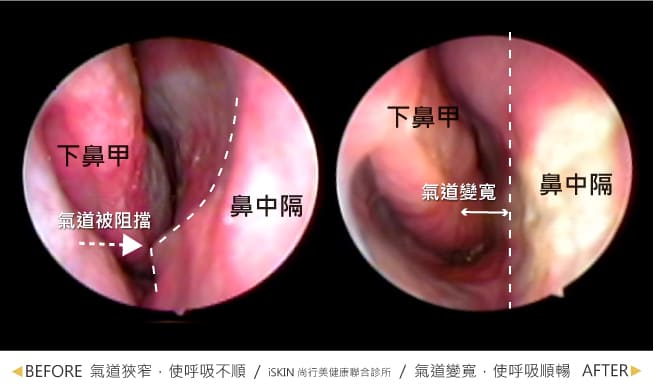

陳鏘文醫師先幫Leo用內視鏡檢查後,原來Leo的鼻中隔都已經歪到左邊去了,難怪Leo的鼻塞怎麼都不會通。尤其現在過年剛結束,季節交替的時刻,塞住的症狀就更加不舒服、難以呼吸的感覺更明顯了。因此,陳醫師當下便建議Leo可以盡快排定手術,把鼻中隔彎曲的狀況處理好,一定可以回到正常生活。

只要能改變現狀當然勢必要做,而且陳醫師是選擇局部麻醉,雖然事後Leo也透漏第一次躺在手術台上,感覺冰冷又安靜,當下真的心裡不知道抖了幾百回,想說改天再來的念頭後,就很簡單的結束了這場「戰役」。然後手術完,Leo第一口的呼吸,就覺得世界原來那麼美好,沒有比鼻塞更痛苦的事情了!鼻中隔嚴重彎曲及下鼻夾肥厚問題,經陳鏘文醫師手術及加上廣達雷射,一次就解決了,現讓氣流量大了快2倍。